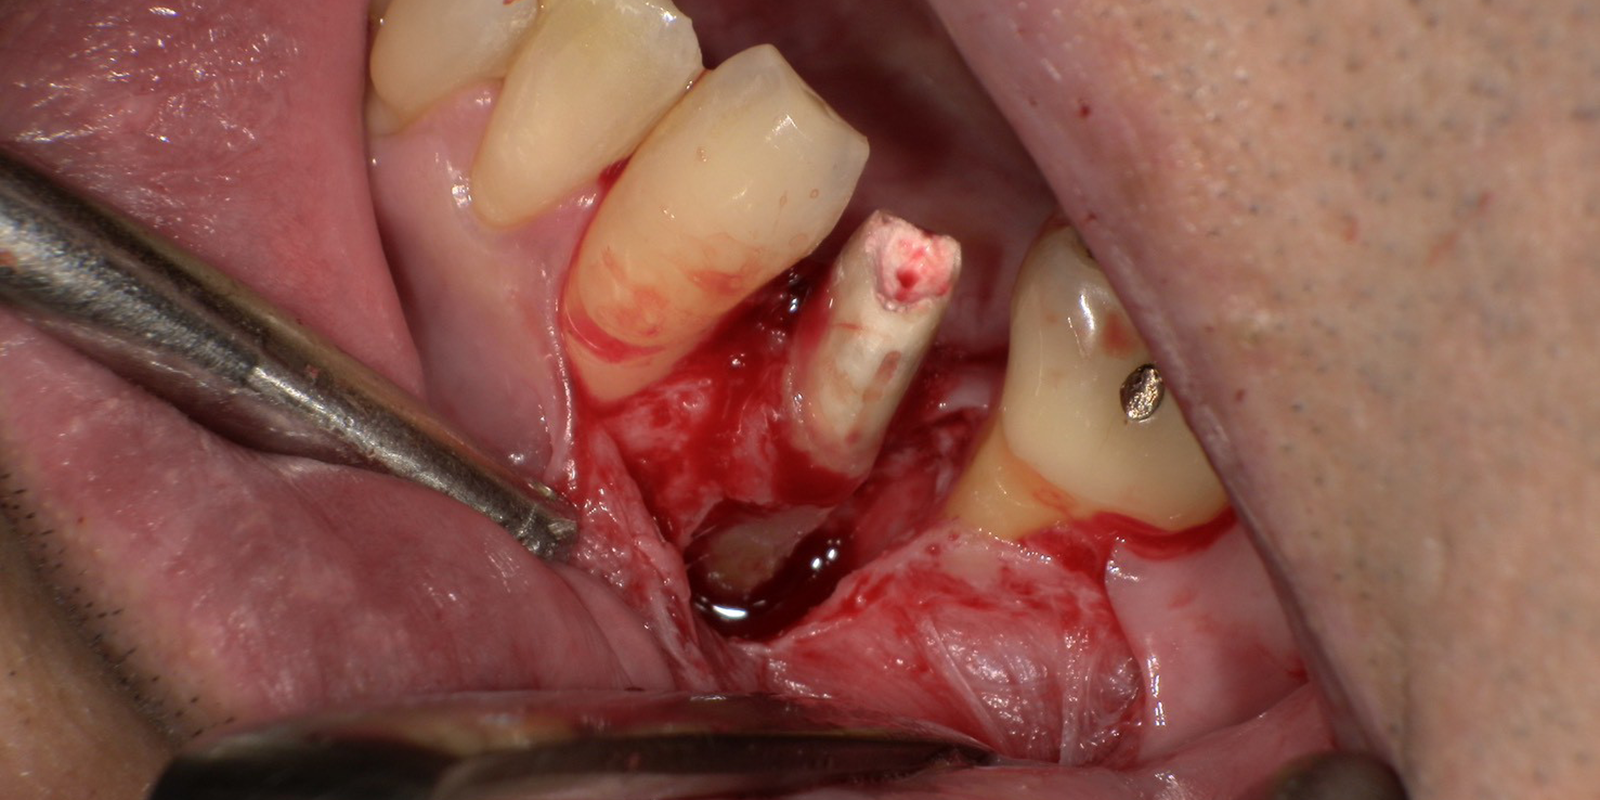

【左下5感染根管治療】と【外科的歯周病治療】

まず根管治療を行いました。精密根管治療が求められましたので、ラバーダム防湿とマイクロスコープは毎回使います。最終的な根管充填剤もMTAと呼ばれる薬剤を選択し、少しでもこの歯を残す治療を行いました。

その後、基本治療をして数値が悪いところ・左下5の周囲は外科的にお掃除します。